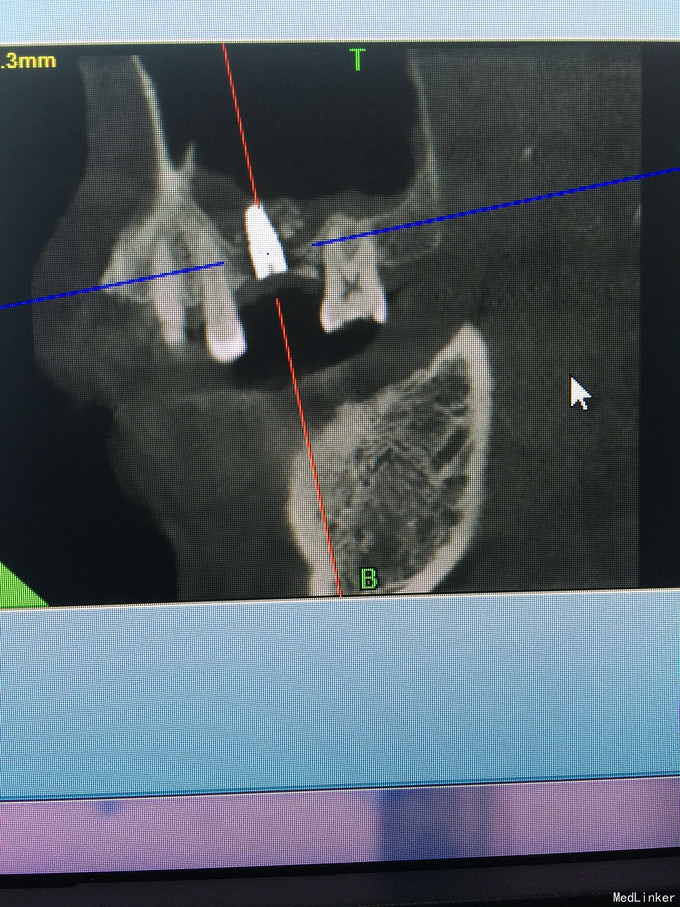

张先生,右上6缺失多年,要求种植

骨量只有2.4毫米

上颌窦内提,同期植入4.1-10植体